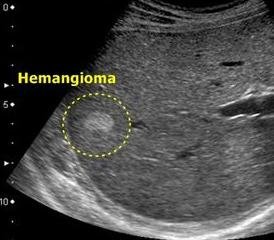

Если показатели указанных методов диагностик будут неинформативны или положительны, то врач может назначить дополнительное обследование — УЗИ печени, которое с помощью доплера устанавливает паренхимы — округлой формы образования в жизненно важном органе. Стоит помнить, что УЗИ не устанавливает диагноз, а лишь предполагает его наличие. Если все-таки опасение по поводу болезни подтвердится, то врач может назначить следующий вид анализа — МРТ печени. Это самый информативный метод исследования в настоящее время, который выявляет точное расположение новообразования, его размеры и уровни жидкости.

Если же и показания МРТ для Вашего лечащего врача не будут служить причиной для постановки диагноза, то доктор может назначить и целиакографию, сцинтиграфию и радиоизотопное исследование. Все это поможет дифференцировать опухоль.